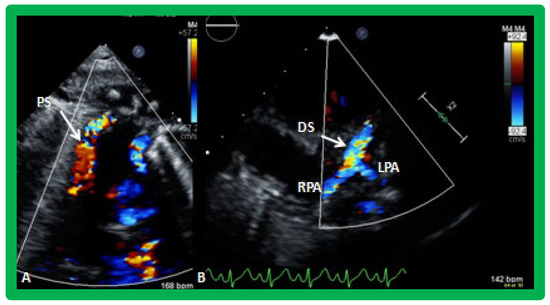

Figure 19. Selected video frames from suprasternal notch view demonstrating proximal shunt (PS) by color flow imaging (A). In a slightly different view, (B), the flow from the distal shunt (DS) into right (RPA) and left (LPA) pulmonary arteries is shown.